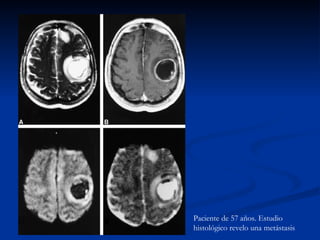

Paciente de 57 años. Estudio histológico revelo una metástasis

Absceso Cerebral Los tumores con necrosis central ( primarios y metastásicos) presentan una marcada hipointensidad en imágenes ponderas en difusión y un mayor coeficiente de difusión aparente

Paciente de 57años. Estudio histológico revelo una metástasis